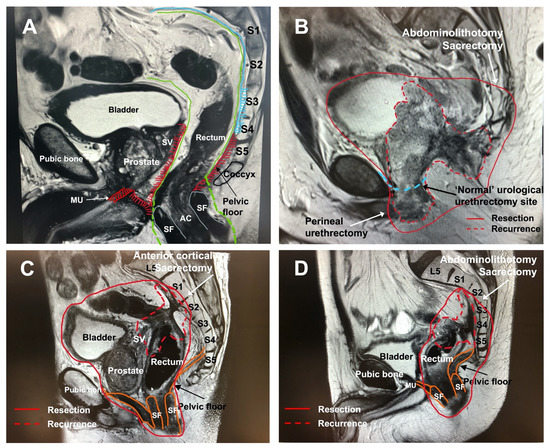

4.1. The Anterior Compartment with or without En-Bloc Pubic Bone Resection

4.2. The Posterior Compartment and En-Bloc Sacrectomy

4.3. Resection of the Lateral Compartment